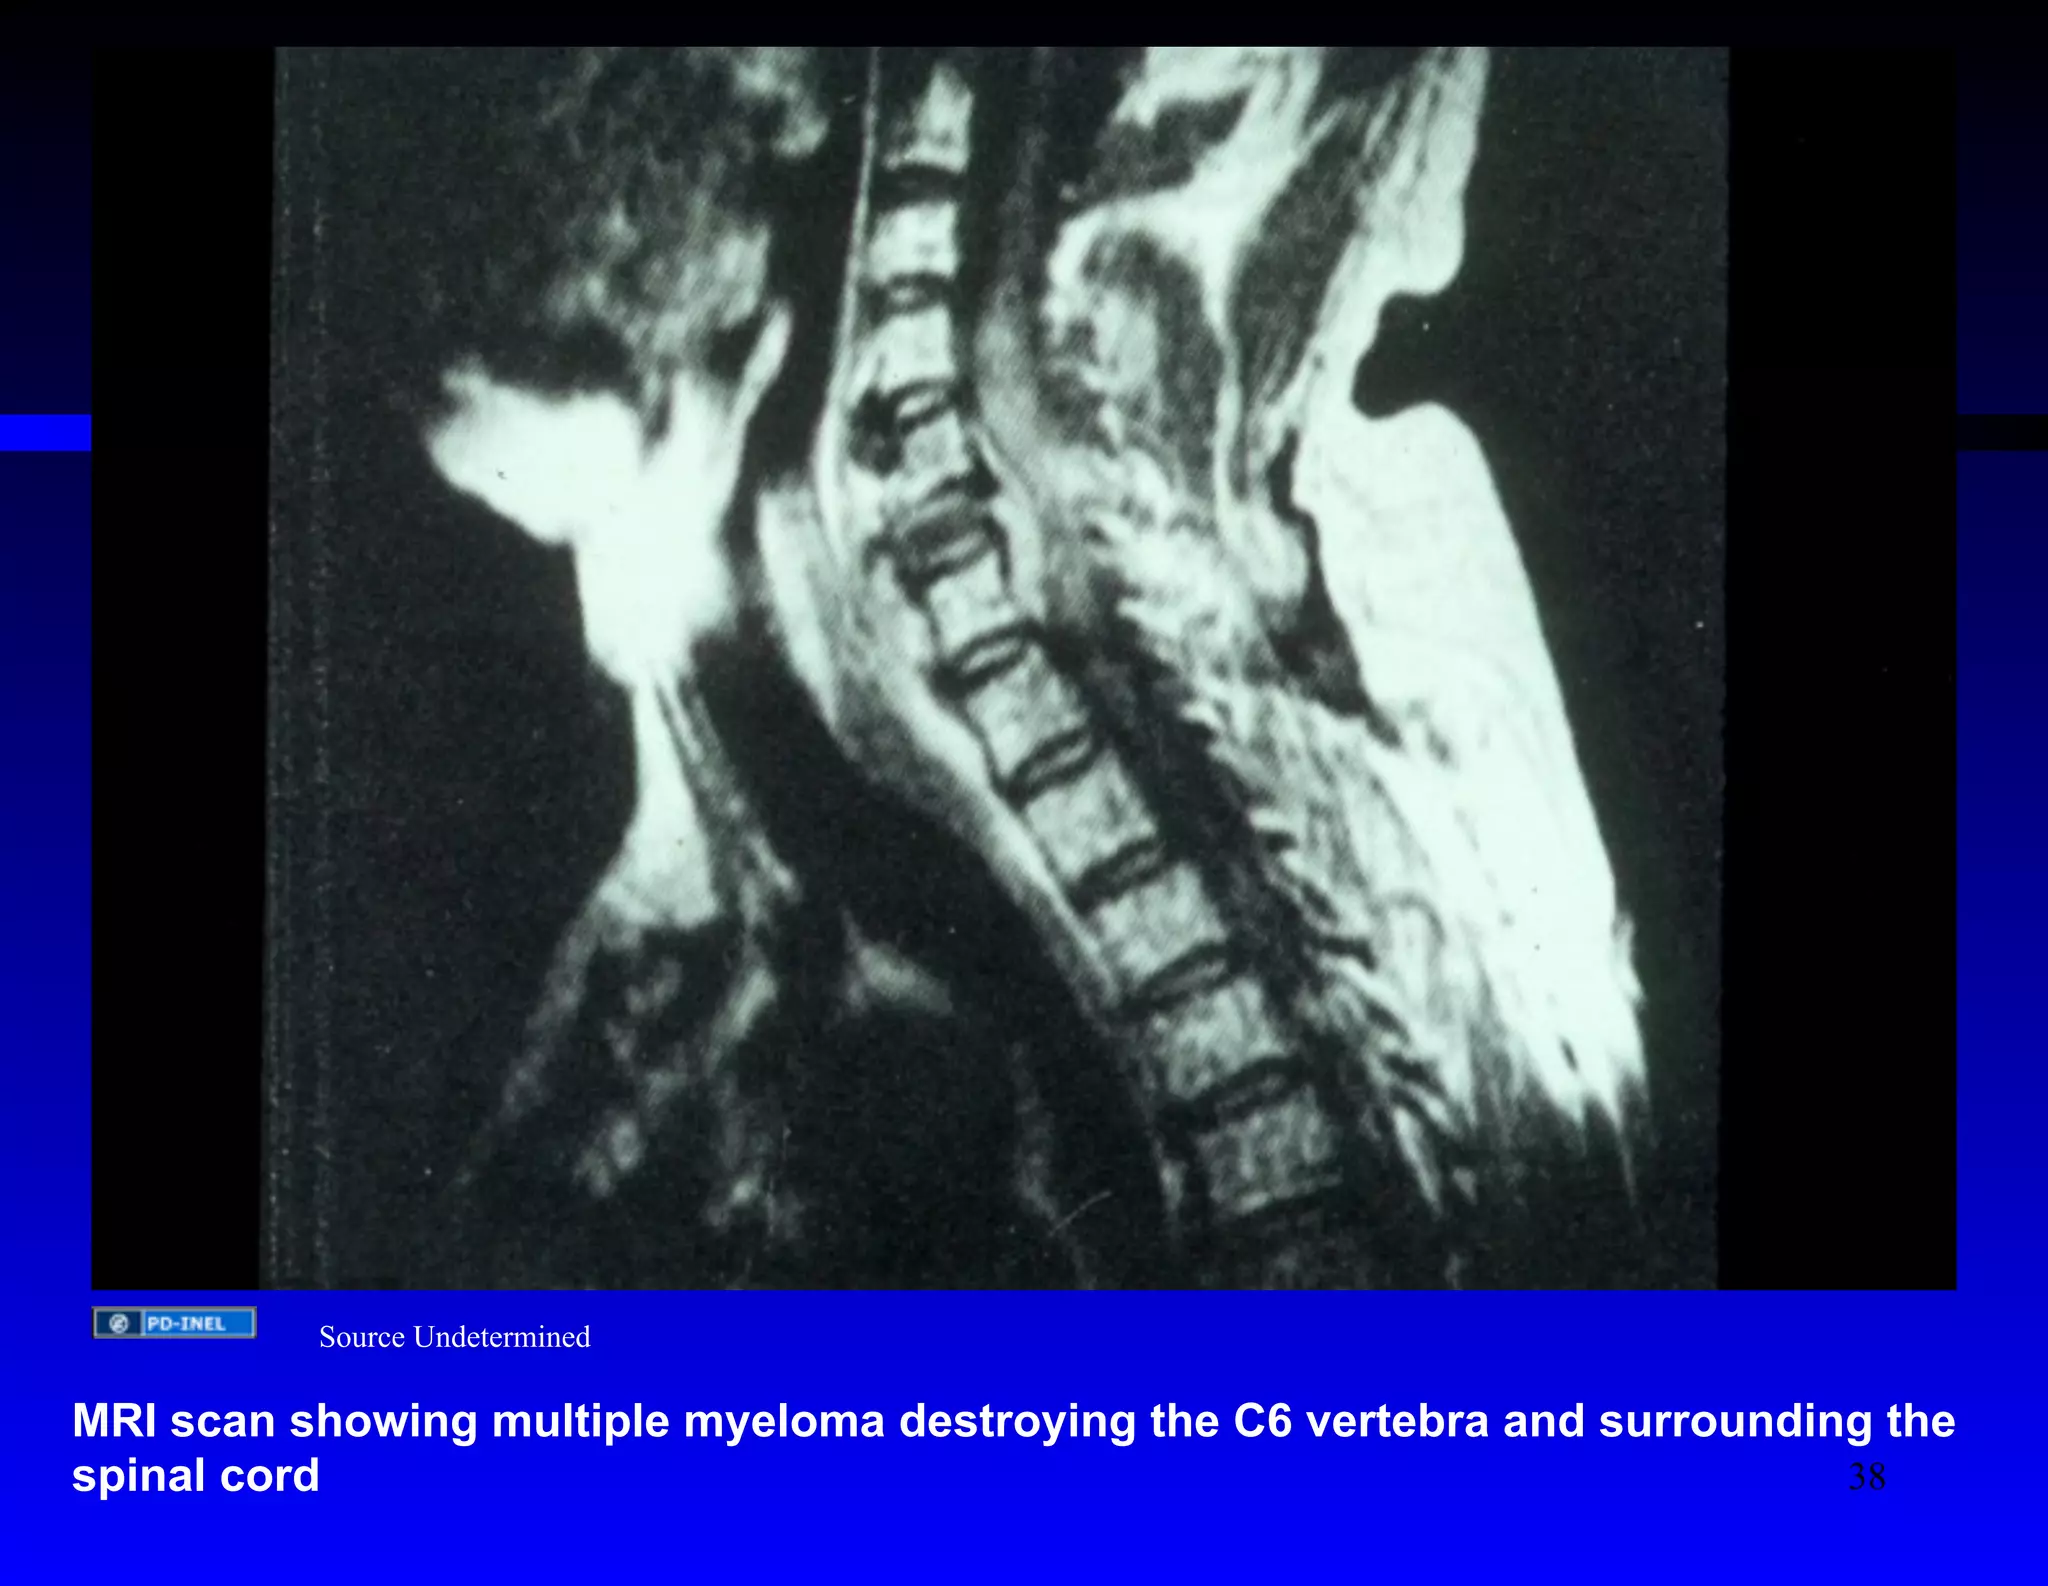

Source Undetermined

MRI scan showing multiple myeloma destroying the C6 vertebra and surrounding the

spinal cord